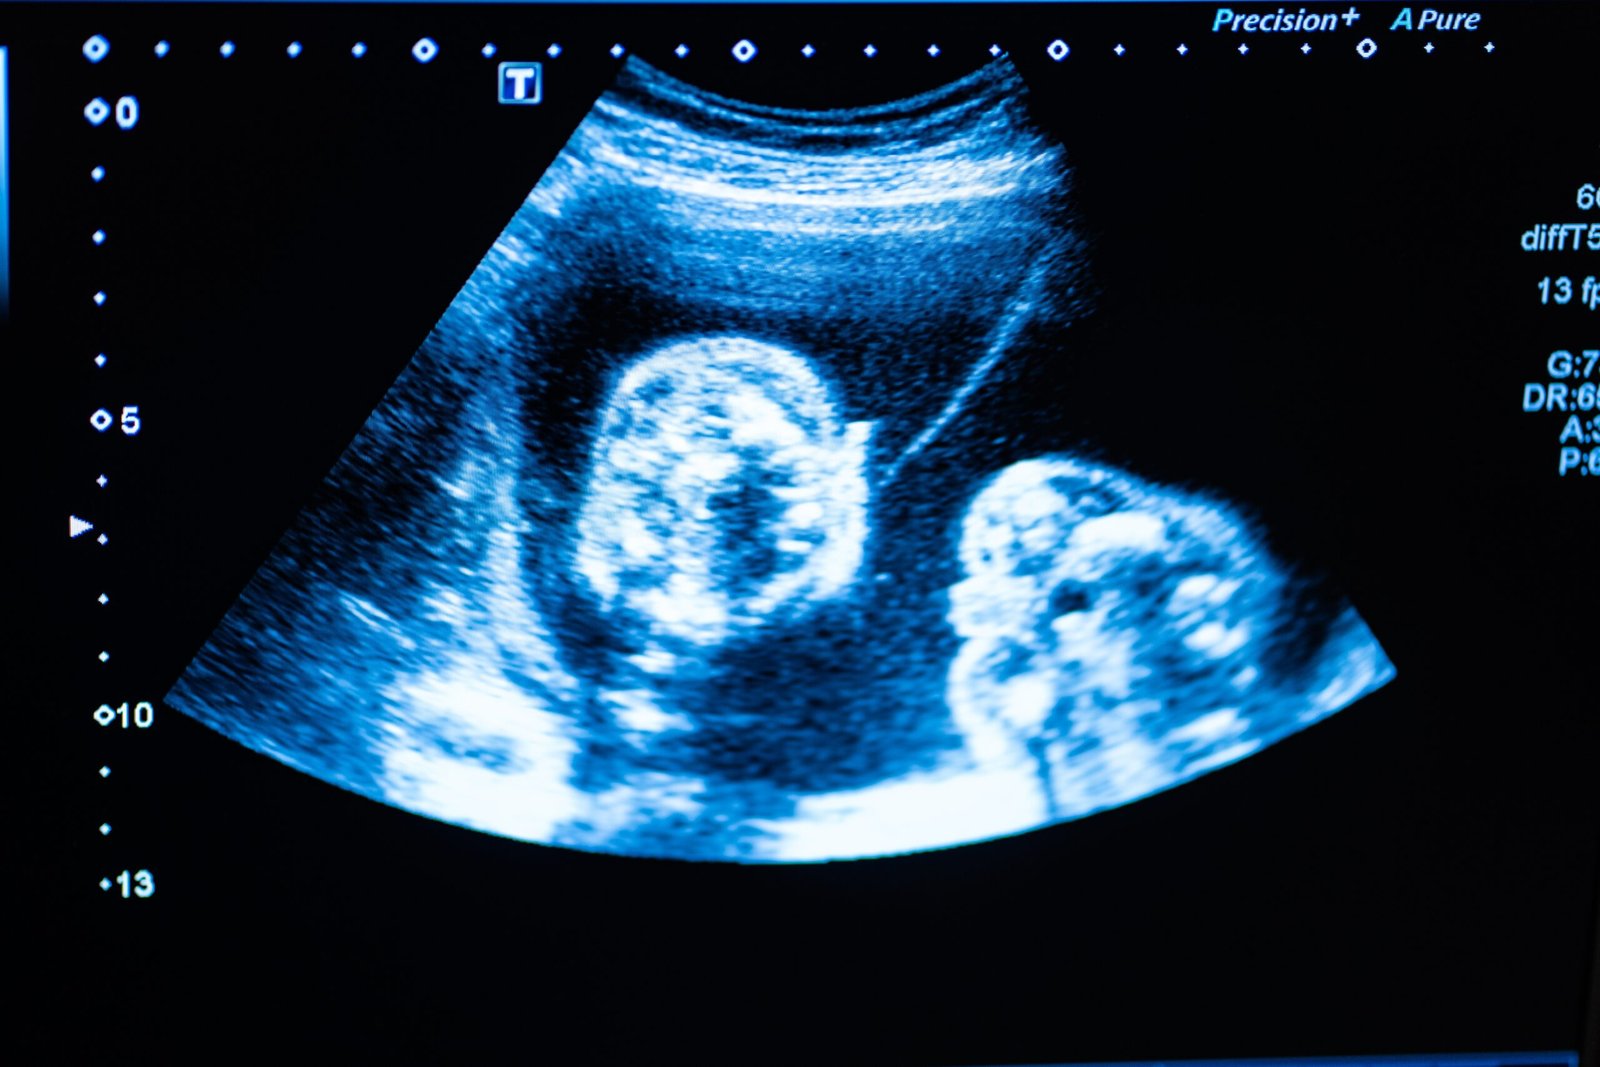

Visualize blood vessels in real time

Assess tissue layers beneath the skin

Identify existing filler and its exact location

This provides critical information that cannot be seen or felt manually, adding an extra layer of safety when it matters most.